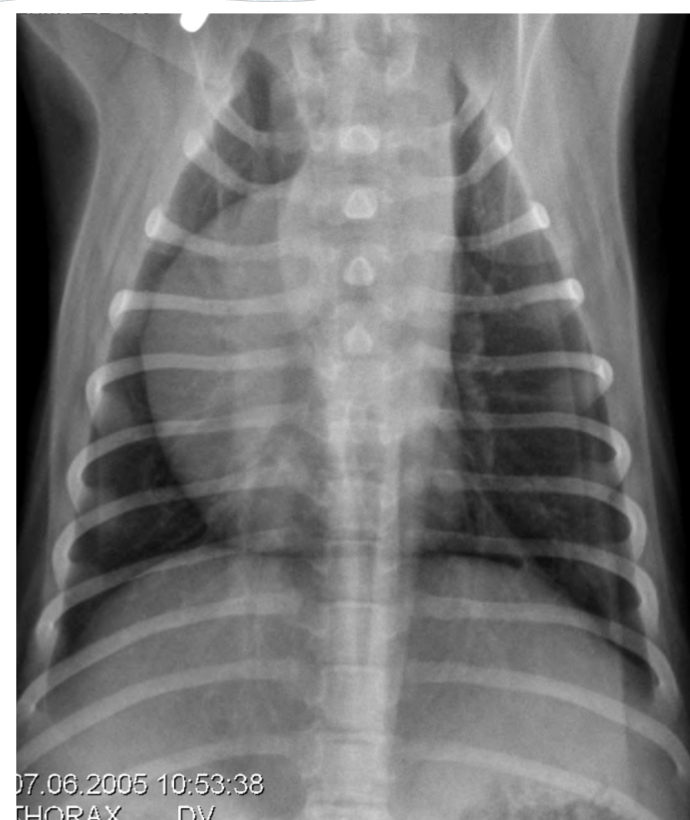

Q

identify 1-2, based on x-ray what is likely dx . Which lobe is affected

A

1. Pulmonary artery

2. Pulmonary vein (enlarged)

Dx: left sided heart failure

Right caudal lung lobe affected